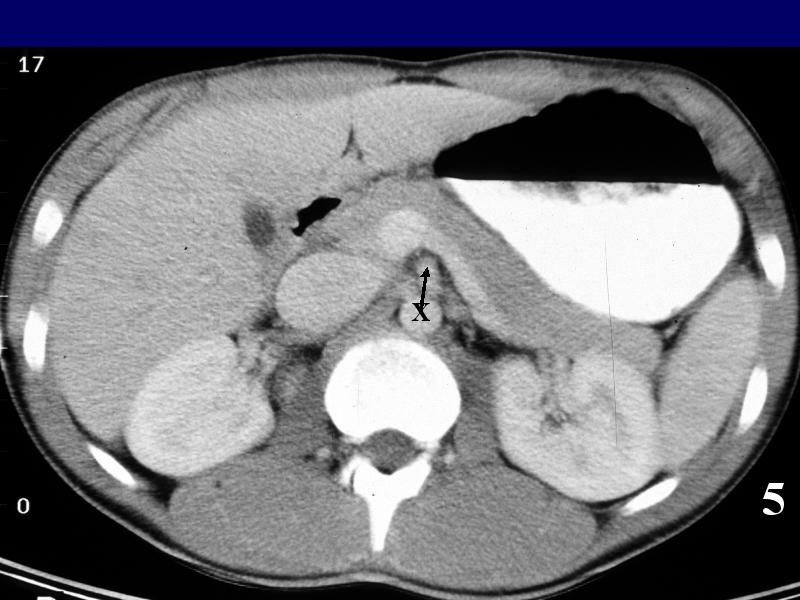

MS 190 CT 16